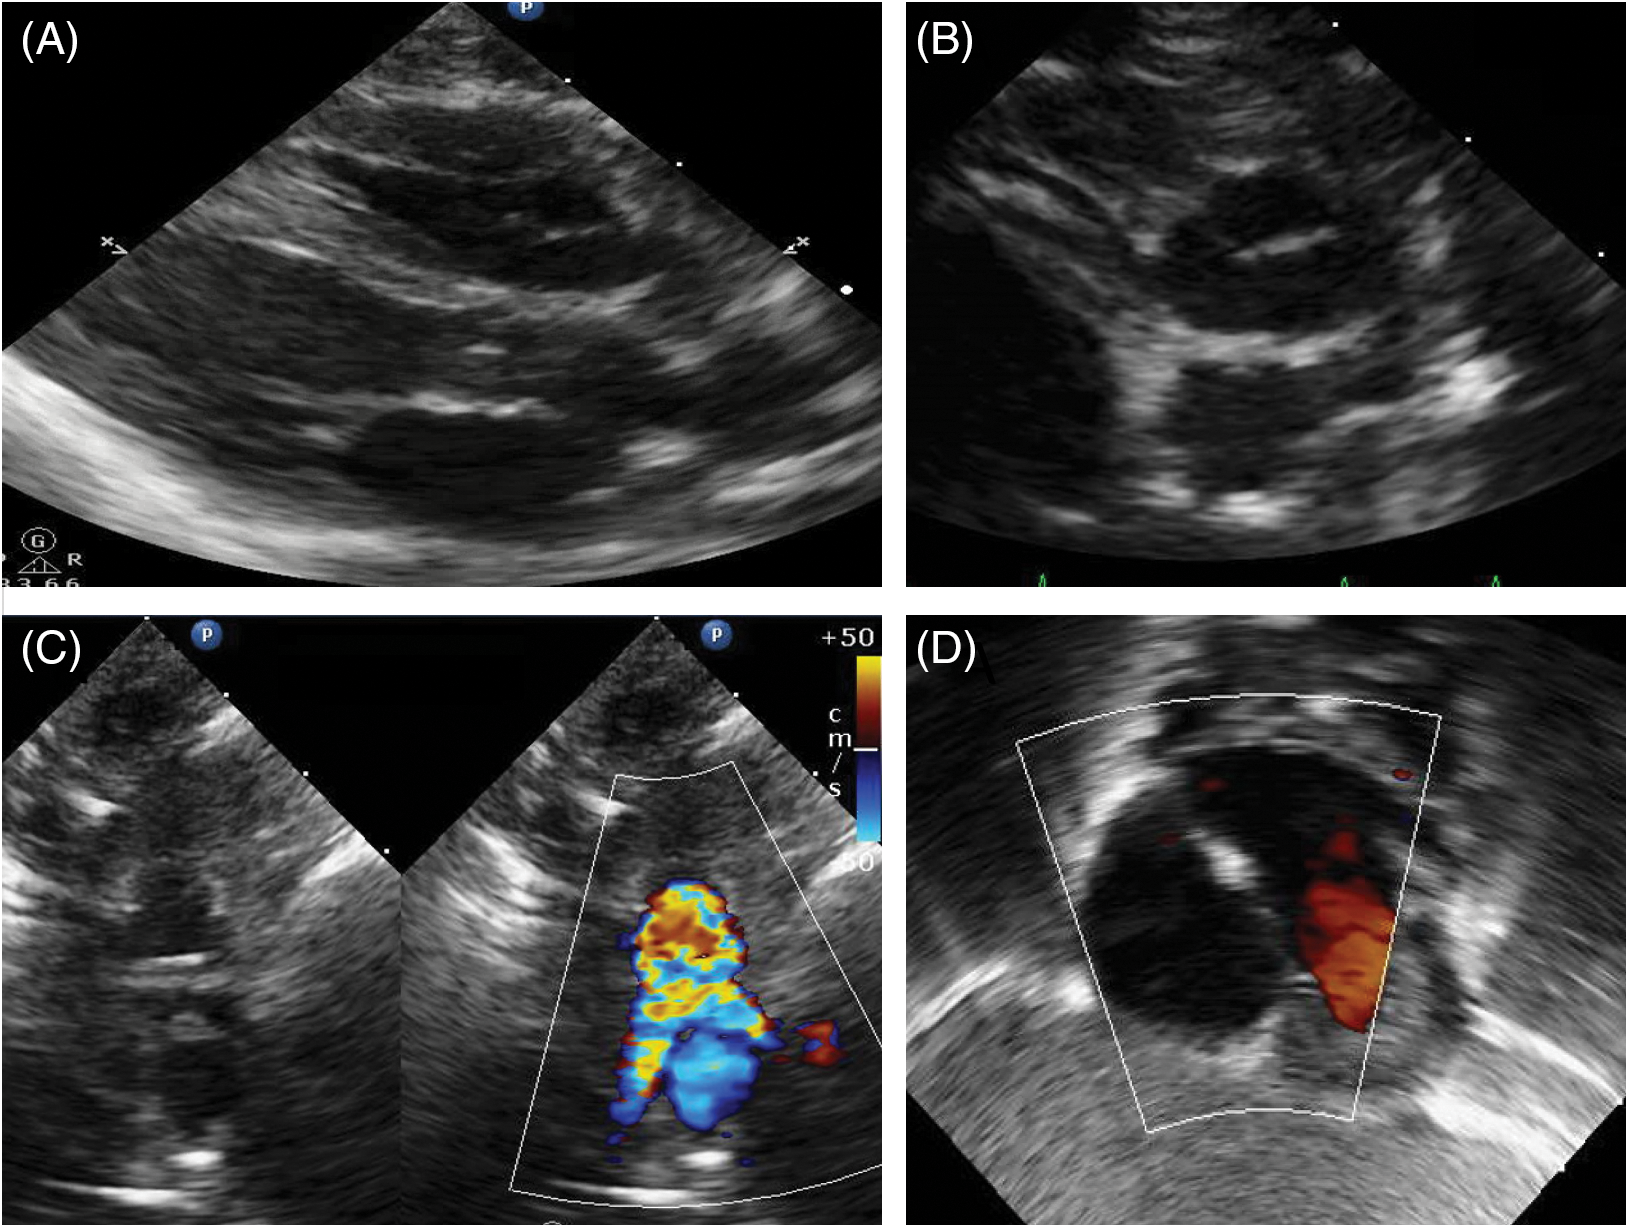

Patient 2 was born at 40 weeks gestation in February 2023 and had a post-natal diagnosis of d-TGA. During feedings at his birth hospital, he was noted to become cyanotic with pulse oximetry confirming oxygen saturations as low as 60%. He was transferred to our hospital and an echocardiogram confirmed the diagnosis of d-TGA with intact ventricular septum. He underwent an ASO with LeCompte maneuver on DOL 4. He did well post-operatively with no major complications and was transferred to the CSU on DOL 7. While he had no concerning findings on his subsequent echocardiograms and successfully transitioned to all feedings by mouth, he remained hypoxic when weaned from the nasal cannula. Fig. 2 demonstrates the pre- and post-operative echocardiographic imaging.

Figure 2: Pre- and post-operative echocardiographic imaging of patient 2. Panel 2A shows parasternal long-axis imaging demonstrating the parallel orientation of the great vessels with the posterior branching vessel being the pulmonary artery. Panel 2B shows the anterior aorta and posterior pulmonary artery, with the right coronary artery arising from and identifying the aorta. Panel 2C shows the characteristic relationship of the great vessels after the LeCompte maneuver with the branch pulmonary arteries straddling the ascending aorta. Panel 2D shows the atrial septum with no residual right to left shunt after patent foramen ovale suture closure